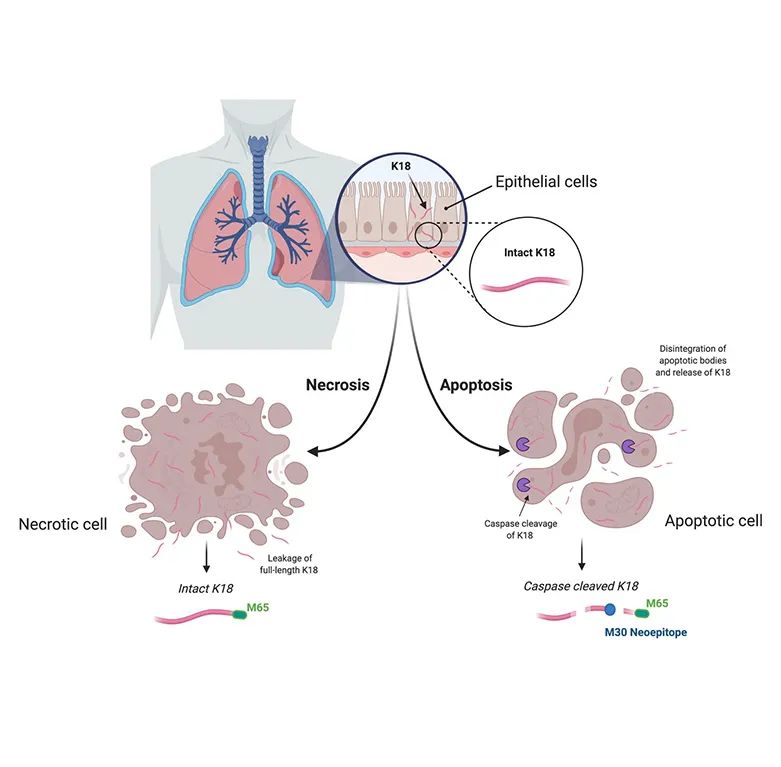

当肝脏受到以上各种损伤因素侵袭时,肝细胞会发生一系列病理变化。这些变化包括细胞膜通透性增加、细胞凋亡或坏死等。不同的毒性刺激会诱发不同的细胞凋亡方式。

CK18是上皮细胞特异性表达的蛋白,有两种表达形式

半胱天冬酶(Caspase)裂解的CK18片段(CK18-M30)和 全长蛋白(CK18-M65)

CK18-M30

是CK18蛋白在上皮细胞凋亡过程中被半胱天冬酶(caspase)裂解产生的片段。在细胞凋亡的早期阶段,细胞内的一系列蛋白酶(如 caspase-3,-6,-7,-9)被激活。这些蛋白酶会特异性地识别 CK18 蛋白上的位点并进行切割,产生含新生抗原决定簇的M30片段。

CK18-M65

是从凋亡或坏死细胞中直接释放的未被裂解的完整CK18蛋白。在肝细胞坏死过程中,细胞会发生肿胀、破裂,细胞内容物包括 CK18 蛋白会非特异性地释放到血液中;同时在凋亡过程中,除了产生 M30片段外,也会有其他的 CK18 裂解产物,M65片段可以综合反映这些过程。所以,通过免疫测定法在人血清中检测M65,可以涵盖肝细胞坏死和凋亡两种情况,其在血液中的水平能够更好地体现总肝损伤的程度。

Mechanism of action of M30 and M65 cell death assays.